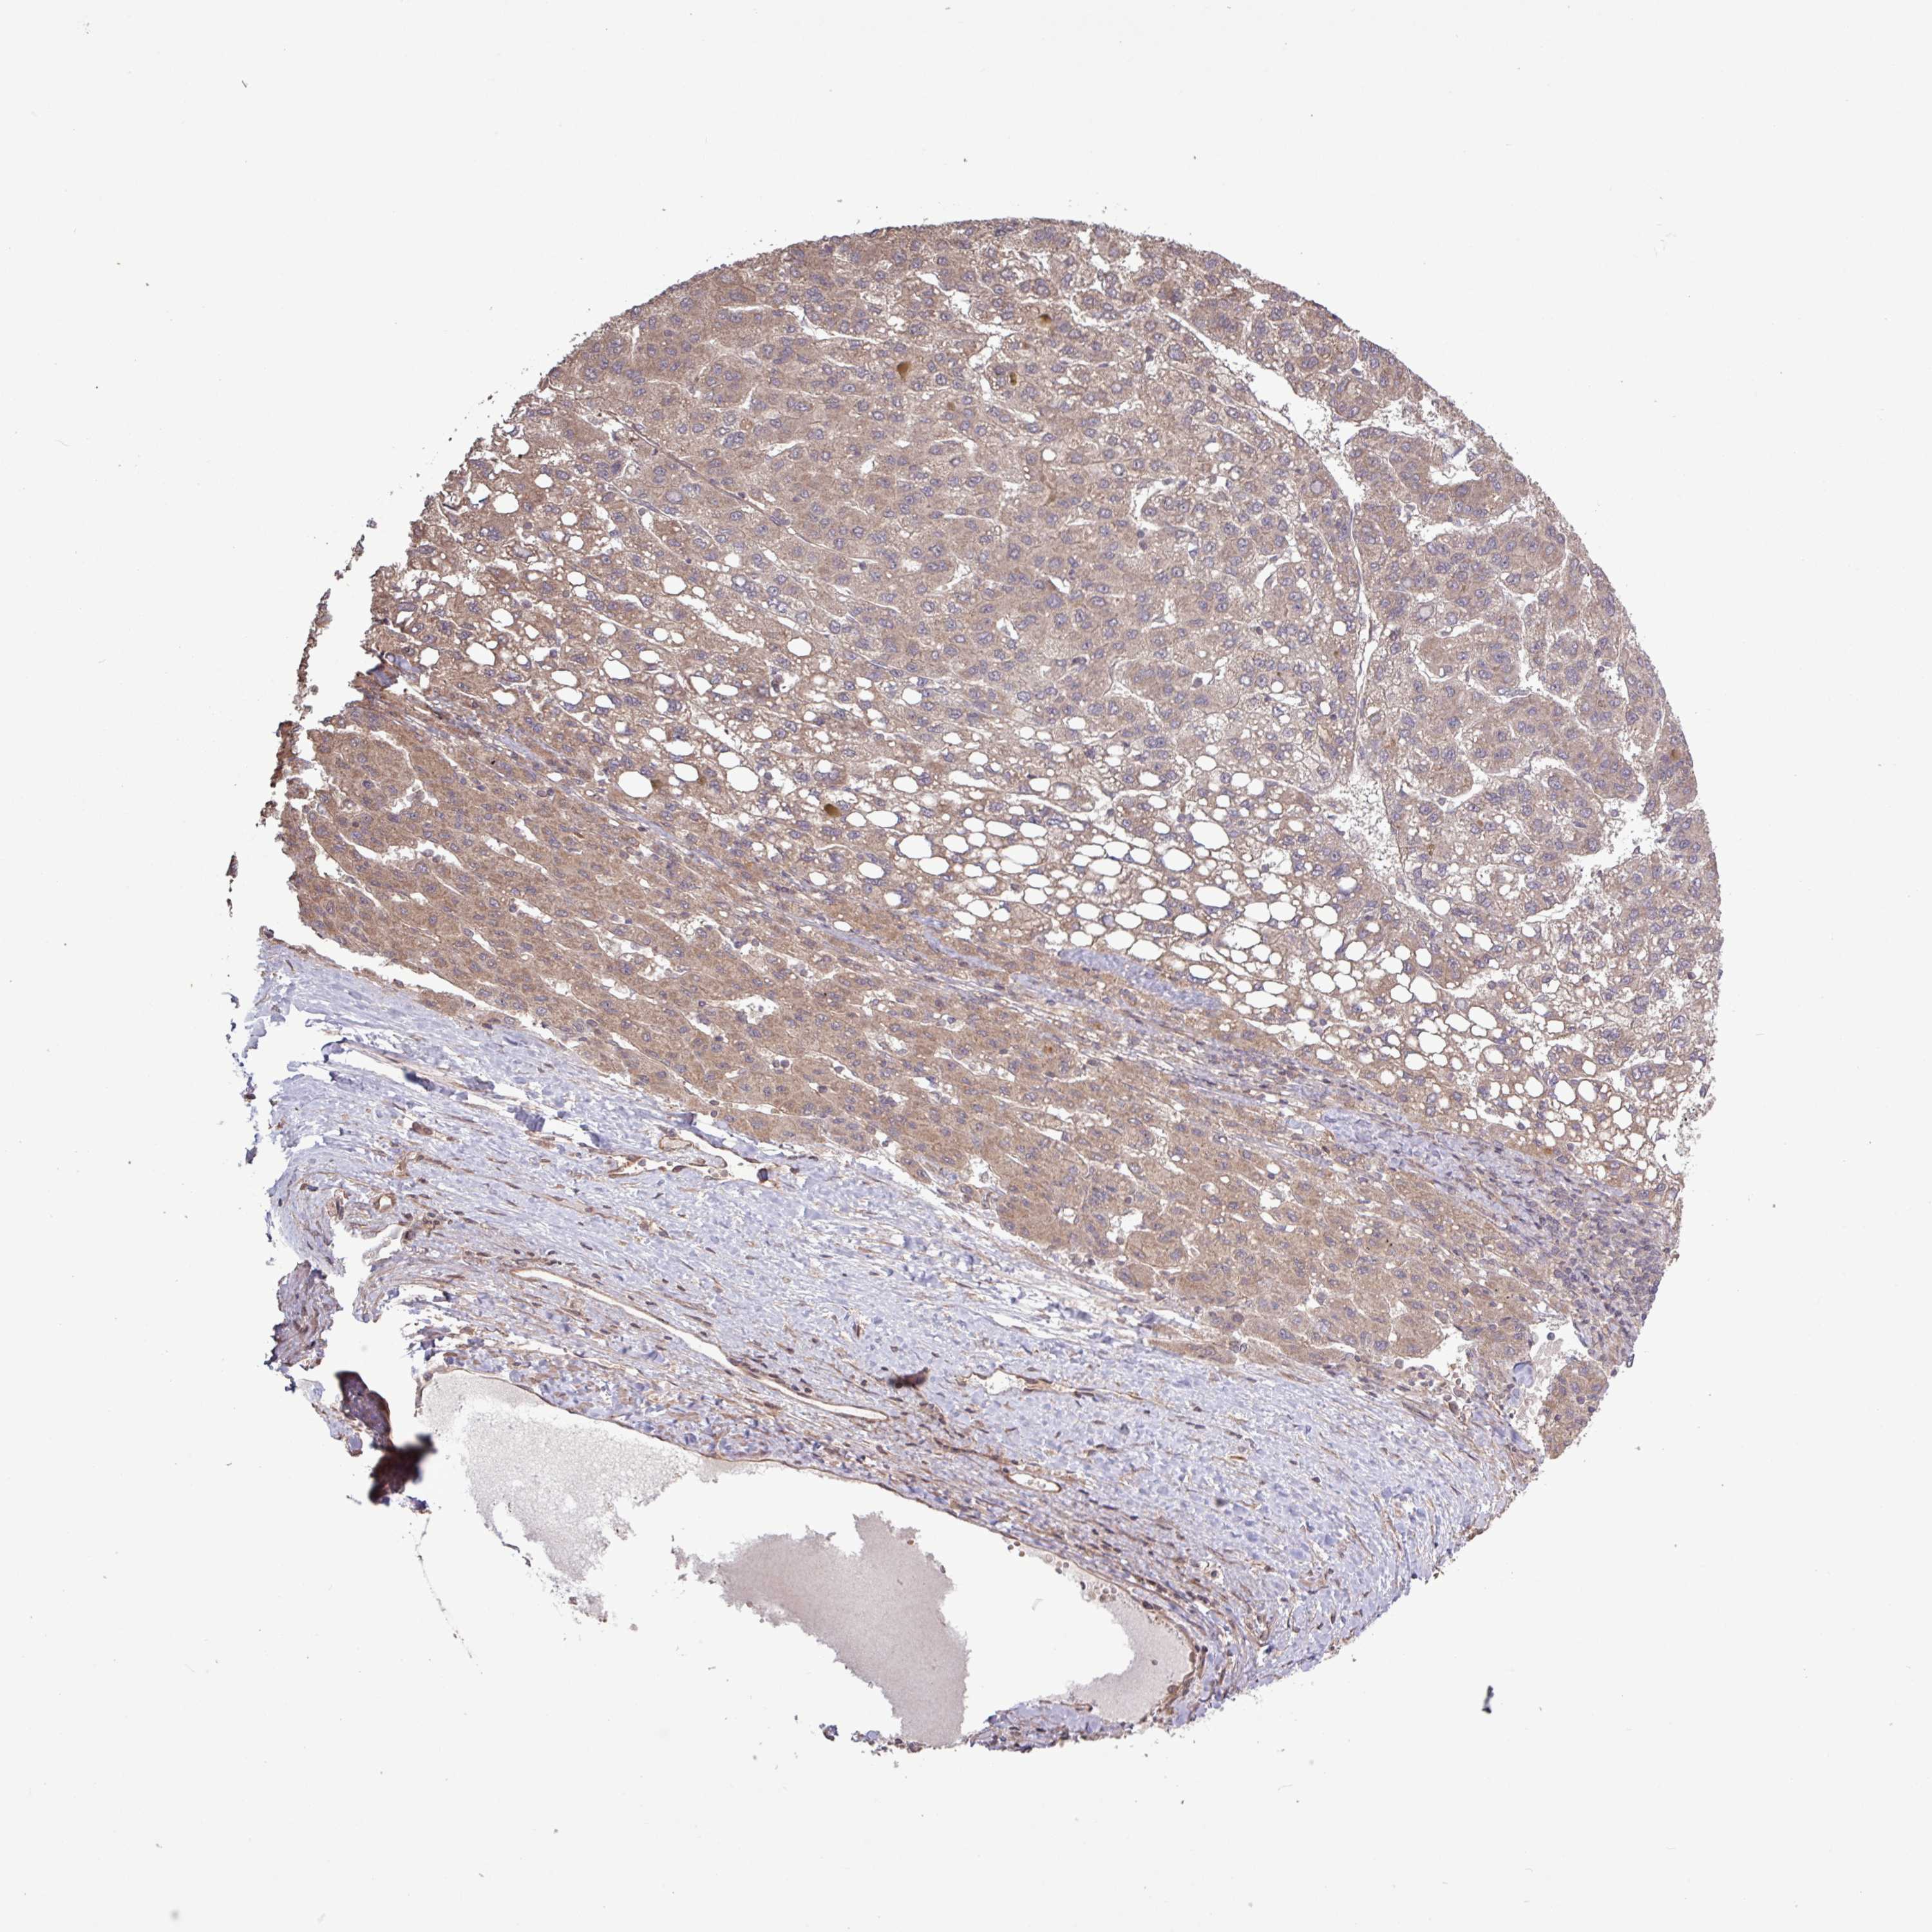

LIVER CANCER - Protein expressioni

A mouse-over function shows sample information and annotation data. Click on an image to view it in a full screen mode. Samples can be filtered based on level of antibody staining by selecting one or several of the following categories: high, medium, low and not detected. The assay and annotation is described here.

Note that samples used for immunohistochemistry by the Human Protein Atlas do not correspond to samples in the TCGA dataset.

Antibody stainingi

Antibody staining in the annotated cell types in the current human tissue is reported as not detected, low, medium, or high, based on conventional immunohistochemistry profiling in selected tissues. This score is based on the combination of the staining intensity and fraction of stained cells.

Each image is clickable and will lead to virtual microscopy that enables deeper exploration of all samples and also displays staining intensity scores, fraction scores and subcellular localization as well as patient and tissue information for each sample.

Antibody HPA045817

Staining

High

Medium

Low

Not detected

Intensity

Strong

Moderate

Weak

Negative

Quantity

>75%

75%-25%

<25%

None

Location

Nuclear

Cytoplasmic/membranous

Cytoplasmic/membranous,nuclear

Carcinoma, Hepatocellular, NOS

Cholangiocarcinoma